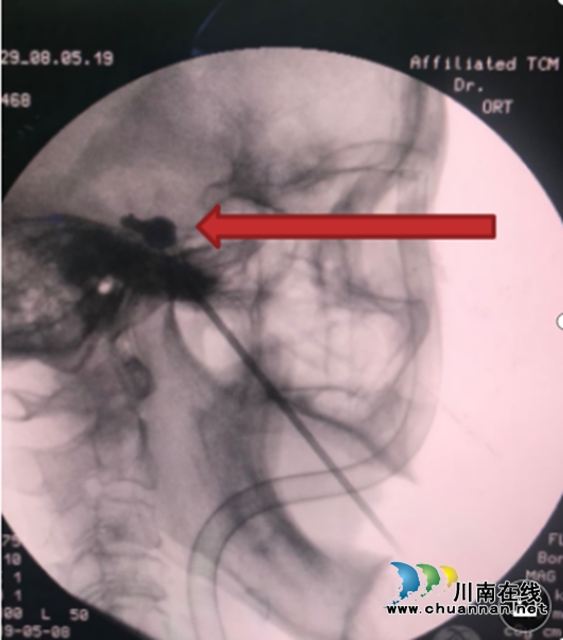

疼痛难忍,拔光了右边的牙齿,但还是无济于事。她来到了西南医科大学附属中医医院。 疼痛难忍  大妈竟被拔光了牙齿 吃饭、刷牙、吹冷风、张嘴笑……王大妈只要做这些事,右侧颌面部就会出现触电般剧烈疼痛。 王大妈介绍,像上述触电般的疼痛已经有10